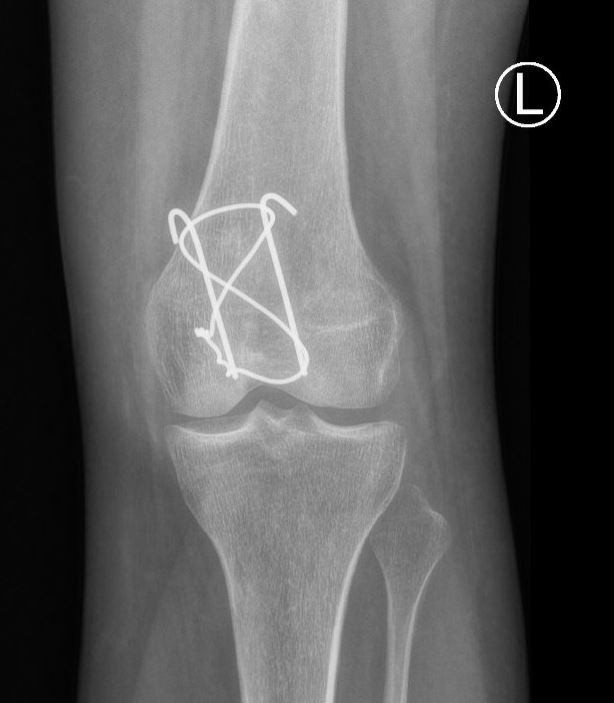

De meeste breuken van de knieschijf zullen operatief vastgezet moeten worden met een zogenaamde ‘Zuggertung’, bestaande uit enkele dunne metalen pinnetjes en een metalen vlechtdraad om de knieschijf heen. Soms worden er ook schroeven gebruikt. Het materiaal wordt geplaatst via een snede aan de voorkant over de knieschijf.

Zoals elke operatie, heeft ook een operatie voor een gebroken knieschijf kans op complicaties, zoals nabloedingen en ontstekingen van de wond, doofheid van de omliggende huid, het loslaten van het fixatie materiaal en het niet goed willen vastgroeien van de breuk. Ook hebben patiënten na een operatie nogal eens last van irritatie van het fixatiemateriaal, omdat het materiaal hier vlak onder de huid ligt. Indien de breuk weer op volledige sterkte is (meestal pas na circa 9-12 maanden) en het fixatiemateriaal geen nut meer heeft, kunt u overwegen om het materiaal weer operatief te laten verwijderen indien u hier klachten van hebt. Indien u geen klachten hebt, kunt u het fixatiemateriaal veilig laten zitten.